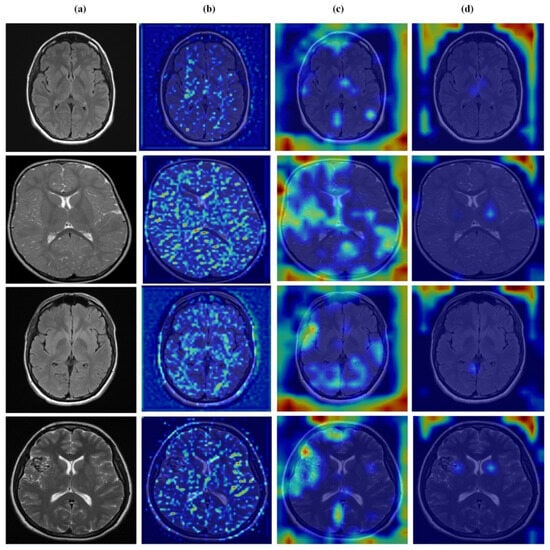

4.7. Feature Learning Analysis

Figure 12, Figure 13, Figure 14 and Figure 15 present Grad-CAM visualizations that trace the hierarchical feature learning of the proposed model across the four classes. Columns are organized as (a) input, (b) high-level features, (c) mid-level features, and (d) low-level features. In (d), the network emphasizes primitive cue edges, intensity transitions, and fine textures capturing sulcal boundaries, skull edges, and generic tissue patterns. Progressing to (c), activations become more structured and context-aware, highlighting coherent anatomical regions and diffuse hyperintense areas that provide spatial context for lesion localization. At (b), class-discriminative focus emerges with responses that contract tumor-centric hotspots for glioma and meningioma and to the sellar region for pituitary cases, while no_tumor images exhibit suppressed high-level responses, reflecting the model’s rejection of false lesion cues. This bottom-to-top progression from generic edges to task-specific evidence explains the model’s improved decision reliability and aligns with the multi-task design that encourages precise, clinically meaningful attention.

Figure 12.

Visual representation of feature activations in no tumor cases. (a) input, (b) low-level features, (c) mid-level features, and (d) high-level features.